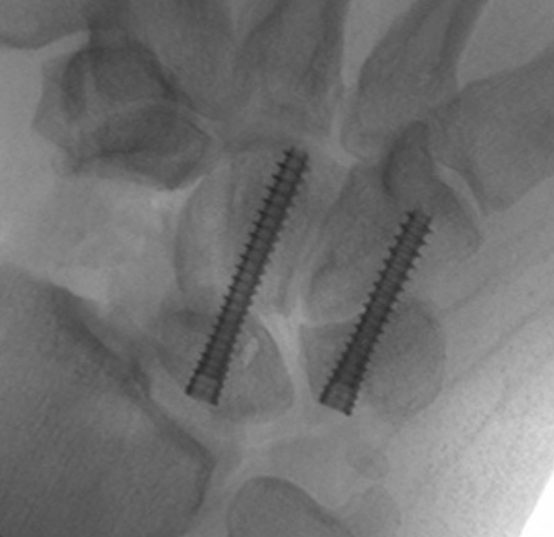

Fixation options

K wires

Headless compression screws

4 corner fusion techniques

4 corner: capitate / lunate screw + triquetrum / hamate / capitate screw

Bi-column: capitate / lunate screw + triquetrum / hamate screw